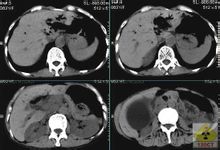

CT检查

CT(computerizedtomography)CT能较好地显示含钙

结石及

肝门区的解剖关系,可提示此综合征与其他疾病鉴别诊断的征象。

CT主要表现为:

胆囊颈增宽;

胆囊外的含钙

结石;靠近

胆囊有一个不规则的囊腔;胰腺段以上

胆管梗阻征象。

肝门区多囊多管征和肝门区扩张的

胆管壁增厚以及肝门区各结构之间的脂肪间隙显示模糊和消失征象,后者是由于胆囊颈或

胆囊管嵌顿

结石引起胆囊管扩张、扭曲和胆囊周围炎的表现。如CT未显示含钙

结石,但有胰上段的

胆管扩张、增厚、

肝门区脂肪间隙显示不清及消失,也应考虑此综合征的可能。但应与肿瘤及其他疾病引起的类似征象鉴别。由于CT横断面的限制,常不能显示胆囊颈/管

结石嵌顿压迫肝总管的直接征象,与超声相比并无更多优势,但随着螺旋CT三维重建技术的开发及在胆

硬化性胆管炎

系疾病中的应用,在此综合征的诊断中具有一定的潜力。